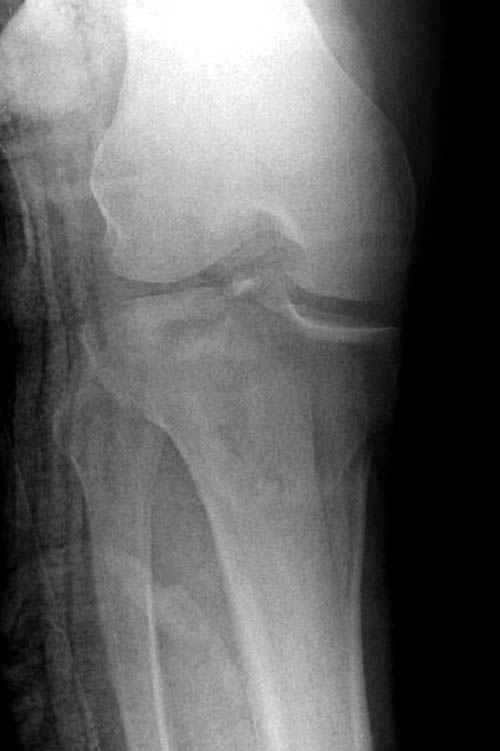

Трудно поверить, что разрекламированная Ортопедическая школа Восточной Украины позволяет такие странные снимки? На прямом снимке сохранен общий контур плато, но не известна судьба импрессии суставной поверхности. На полубоковой?, оставлен без репозиции задне-медиальный отдел, и навряд ли после такой фиксации можно удовлетвориться результатом.

Такая ситуация характерна для многих, когда принимается ошибочное решение, т.е пытаются фиксировать одним имплантом переломы двух мыщелков. Латеральная пластина приемлема только для тех случаев, когда сохраняется интактным медиальный диафизарный кортекс и отсутствует фрагментация на верхушке медиального перелома.

Представленные снимки не информативны, нужны отдельные качественные снимки коленного сустава и голени без ротации.

Надеюсь, представленные снимки разных случаев помогут разобраться в тактике, и критика примется без личной обиды.